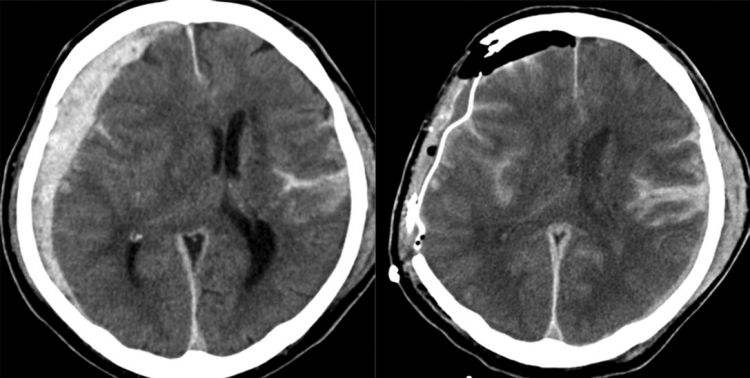

急性脑疝的临床表现?

症状小脑幕切迹疝时,颅内压增高症状表现为剧烈头痛及频繁呕吐,其程度较在脑疝前更形加剧,并有烦躁不安意识改变表现为嗜睡浅昏迷以至昏迷,对外界的刺激反应迟钝或消失瞳孔改变表现为两侧瞳孔不等大,初起时病侧瞳孔略缩小,光反应...